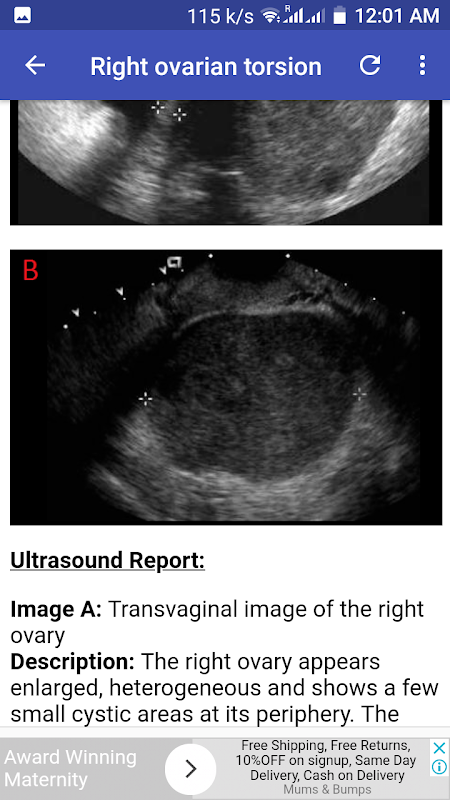

التواء المبيض الأيمن